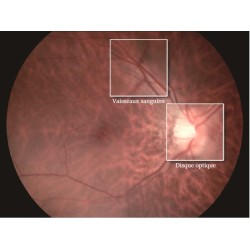

L’OPT-RNM61 fournit des images de fond d'œil haute résolution, la résolution d'image pouvant atteindre 12 méga pixels. Il fait le diagnostic des lésions précoces plus précises et aussi essentiels pour le diagnostic des maladies de la rétine, comme la rétinopathie diabétique, le glaucome et la dégénérescence maculaire.

Non-mydriatique

La dimension minimale de la pupille avec le OPT-RNM61 est φ3.0mm. 20 minutes de dilatation sont économisées, et le risque patient est inexistant.